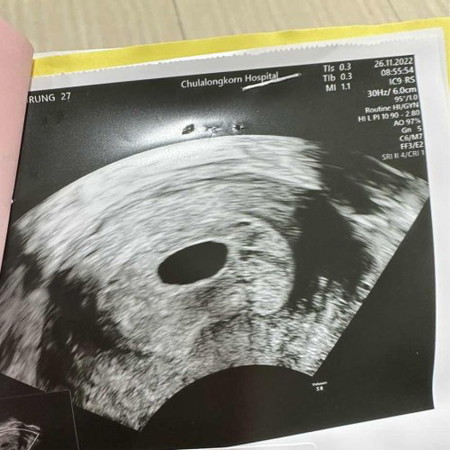

ท้อง7สัปดาห์ 5 วัน เจอแต่ถุงครรภ์ที่ใหญ่ขึ้น มีแม่ๆท่านไหนเคยผ่านประสบการณ์นี้มาบ้างคะคะ